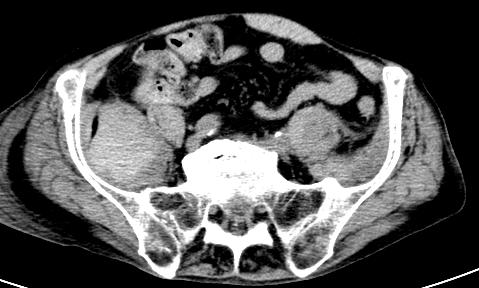

CECT – arterial phase: no sign of acut exravasation (bleeding)

Typical localisation of intramuscular bleeding in elderly patients.

Other frequent localisations: psoas muscle, abdominal wall, quadriceps femoris muscle.